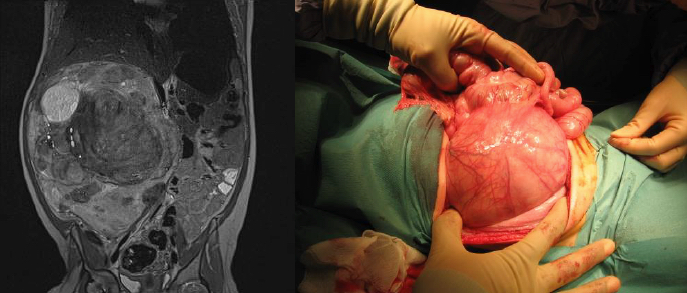

Extrofia vesical masculina: La placa uretral está abierta y se extiende a lo largo del falo corto, ancho y con curvatura dorsal. El glande está abierto y es plano. En ocasiones pueden existir variaciones de la extrofia clásica, como se ve en la figura 1, donde existe apertura de la placa vesical, pero con el pubis y pene intactos.

Extrofia de Cloaca: Los músculos rectos y los huesos del pubis están separados. La vejiga está abierta en la pared abdominal inferior y dividida en 2 mitades adyacentes al segmento expuesto del ciego. Los orificios que comunican el íleon terminal, el apéndice (uno o dos) y el intestino distal son evidentes al interior de la placa cecal y el Íleon terminal puede prolapsarse como un “tronco” a través de ésta. Se presenta con ano imperforado y puede asociarse a onfalocele. Un 95% presenta mielodisplasia y un 65% tiene una malformación de las extremidades inferiores. En hombres, el falo generalmente es bífido y pequeño, con cada hemiglande ubicado caudal a cada hemivejiga, o puede estar ausente. En mujeres, el clítoris es bífido y puede haber dos hemivaginas con un útero bicorne. Las figuras 4 y 5 muestran el aspecto preoperatorio de una extrofia vesical